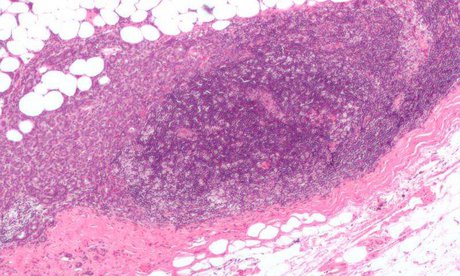

مشاور فرماندار کهگیلویه در امور بانوان از اجرای طرح غربالگری سرطان سینه زنان در کهگیلویه خبر داد.

«الهه شکیبایی» در گفتوگو با خبرنگار خبرگزاری دانشجویان ایران(ایسنا)- منطقه کهگیلویه و بویراحمد از اجرای طرح تست غربالگری سرطان سینه زنان در کهگیلویه خبر داد و گفت: با همکاری شبکه بهداشت تست سرطان سینه زنان را در همه روستاهای بخش مرکزی کهگیلویه و خود شهر دهدشت اجرا میکنیم.

وی خاطرنشان کرد: این طرح برای نخستین بار در روستای کلایه سفلی بهعنوان پایلوت با حضور دو متخصص ماما آغاز به کار میکند.

شکیبایی اجرای این طرح در مرحله اول را رایگان دانست و خاطرنشان کرد: اگر در ابتدای این طرح تشخیص داده شود کسانی مشکل دارند با ارجاع آنها به ماموگرافی در بحث هزینههای آنها کمک میشود.

به گفته وی، این طرح در روستاهای بالای 50 خانوار و در میان افراد بالای 20 سال اجرا میشود.